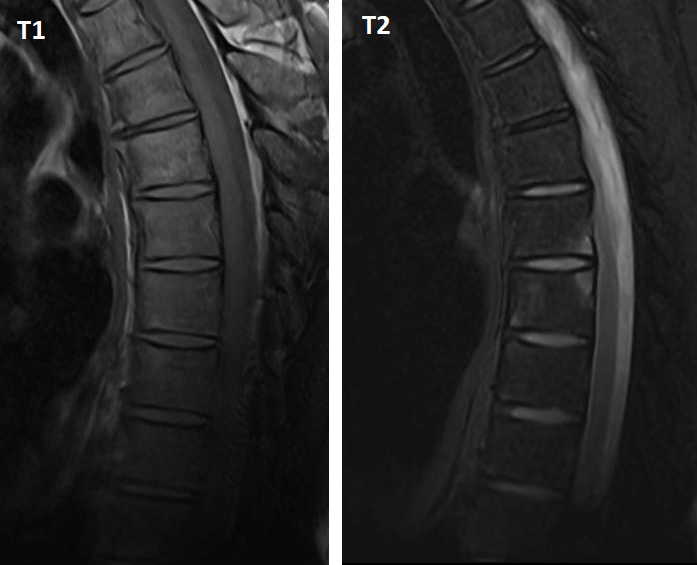

Voici des IRM en séquences T1 et T2 avec suppression du signal de la graisse (Dixon water) :

Figure 2 (Salomé Abdellaoui, La Revue du Praticien)

La vertèbre T6 montre deux coins inflammatoires : antéro-inférieur et postéro-supérieur.

L’IRM rachidienne montre de nombreux coins inflammatoires en hypersignal T2, qui témoignent d’une atteinte enthésitique au rachis. On les distingue des coins « graisseux » qui apparaissent en hypersignal T1 et en hypersignal T2 ou iso-signal sur les séquences avec suppression du signal de la graisse.